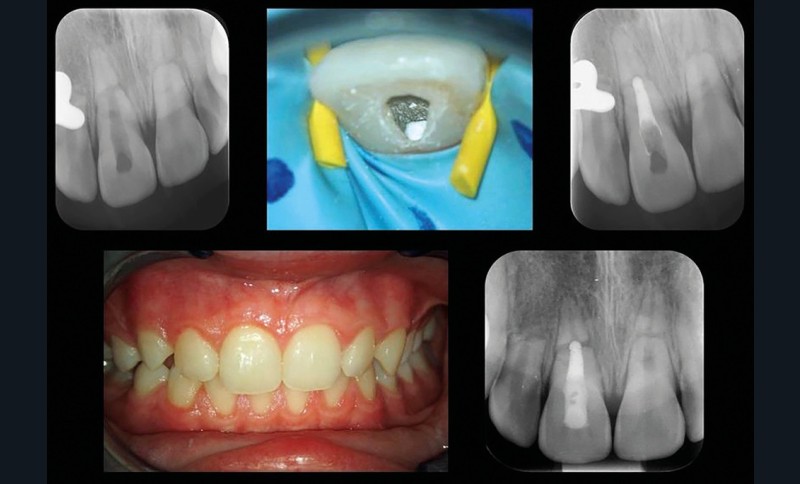

Grâce à ce cliché radiologique, une décision thérapeutique éclairée peut être prise. A savoir : la situation ne peut pas rester comme telle si l’on souhaite obtenir une guérison. Il est alors nécessaire de déposer la première contention et de repositionner convenablement les dents sous anesthésie locale aussitôt que possible puis de placer une nouvelle contention. Cela est indispensable afin d’espérer un pronostic favorable (fig. 4).

Dans cet exemple, le suivi du cas est essentiel, comme pour tous les cas de traumatologie dentaire. Ici, une prise en charge endodontique de la 11 a été nécessaire quelques mois après la dépose de la contention. Le suivi clinique a guidé cette décision thérapeutique. La 11 ne répondait plus aux tests de sensibilité pulpaire (test de sensibilité thermique au froid et test électrique négatifs), la dent présentait également une décoloration coronaire et une sensibilité à la percussion indiquant que la pulpe de la 11 était nécrosée.

Cette nécrose faisant suite à une fracture corono-radiculaire complète et une luxation du fragment coronaire, il était recommandé de réaliser au moins une séance de temporisation à l’hydroxyde de calcium, avant d’obturer définitivement le canal radiculaire à l’aide d’un matériau dit « bioactif ». Dans ce cas-ci, du RRM putty a été utilisé, avant de placer un composite dans la chambre pulpaire, durant la même séance (fig. 5).